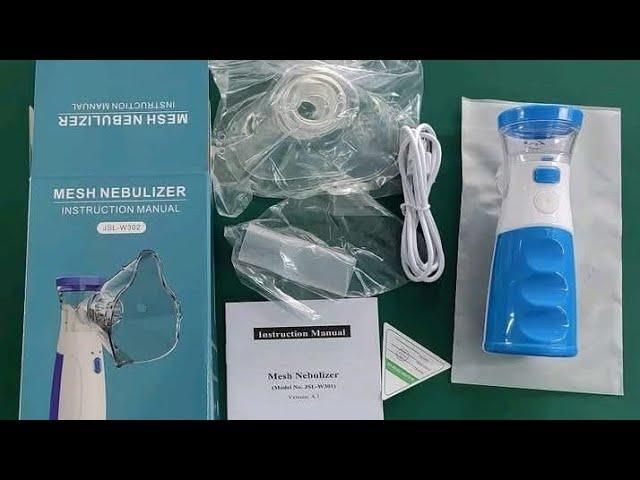

Portable Ultrasonic Rechargeable Mesh Nebulizer Machine

Regular price

Rs. 599.00 INR

Regular price

Rs. 999.00 INR

Sale price

Rs. 599.00 INR